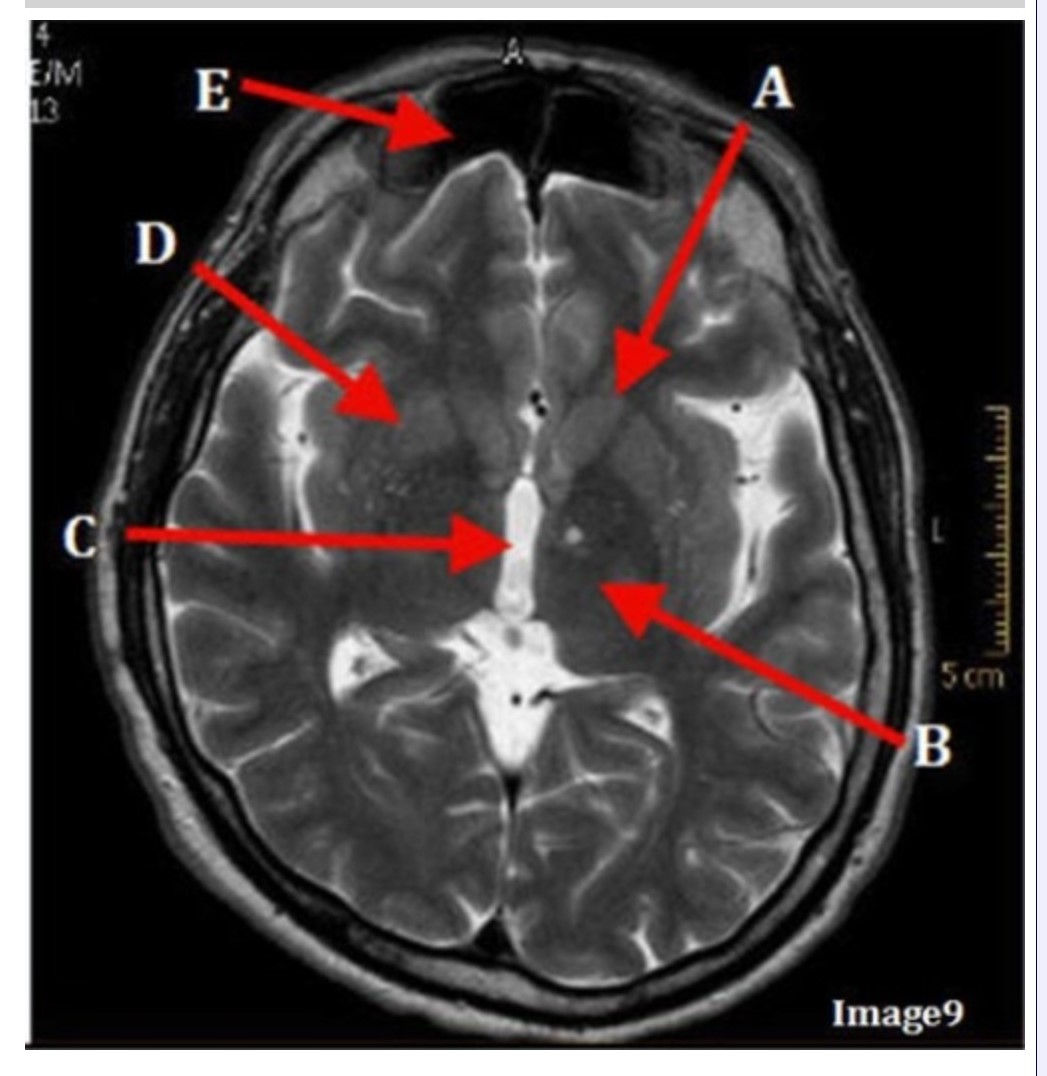

Letter C in Image 9 is pointing to:

A. Third ventricle

B. Thalamus

C. Lentiform nucleus

D. Caudate nucleus

Letter B in Image 9 is pointing to:

A. Third ventricle

B. Thalamus

C. Lentiform nucleus

D. Caudate nucleus

Letter D in Image 9 is pointing to:

A. Third ventricle

B. Thalamus

C. Lentiform nucleus

D. Caudate nucleus

Letter E in Image 9 is pointing to:

A. Maxillary sinus

B. Sphenoid sinus

C. Frontal sinus

D. Ethmoid sinus

Letter A in Image 9 is pointing to:

A. Third ventricle

B. Thalamus

C. Lentiform nucleus

D. Caudate nucleus

Image 9 is an example of a _____ weighted sequence acquired in the _______ scan plane.

A. T1; Axial

B. T2 FLAIR; Sagittal

C. T2; Axial

D. T2; Coronal